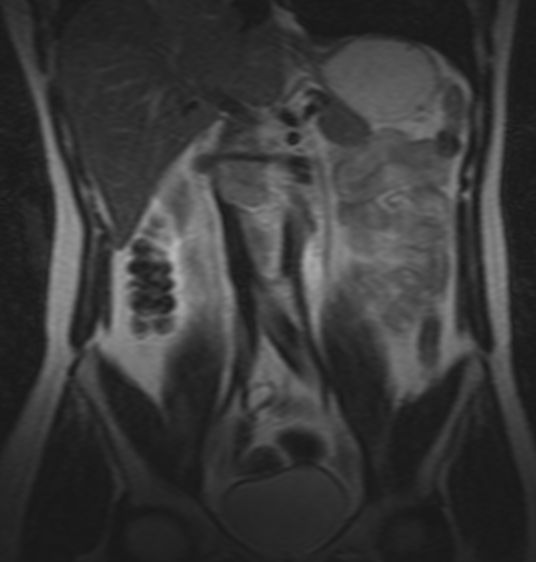

Rezidiv 1 Jahr nach follikulärem Lymphom

MRT